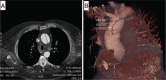

Results: Of the 160 IgG4-RD patients in this cohort, 36 (22.5%) had large-vessel involvement. The mean age at disease onset of the patients with large-vessel IgG4-RD was 54.6 years. Twenty-eight patients (78%) were male and 8 (22%) were female. Thirteen patients (36%) had primary IgG4-related vasculitis and aortitis with aneurysm formation comprised the most common manifestation. This affected 5.6% of the entire IgG4-RD cohort and was observed in the thoracic aorta in 8 patients, the abdominal aorta in 4, and both the thoracic and abdominal aorta in 3. Three of these aneurysms were complicated by aortic dissection or contained perforation. Periaortitis secondary to RPF accounted for 27 of 29 patients (93%) of secondary vascular involvement by IgG4-RD. Only 5 patients demonstrated evidence of both primary and secondary blood vessel involvement. Of those treated with rituximab, a majority responded positively.

Conclusions: IgG4-RD is a distinctive, unique, and treatable cause of large-vessel vasculitis. It can also involve blood vessels secondary to perivascular tumefactive lesions. The most common manifestation of IgG4-related vasculitis is aortitis with aneurysm formation. The most common secondary vascular manifestation is periaortitis with relative sparing of the aortic wall. Both primary vasculitis and secondary vascular involvement respond well to B cell depletion therapy.